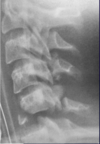

Fratura compressiva da coluna lombar

Causa achatamento do corpo e acunhamento geralmente anterior.

Tipo mais comum de fratura da coluna lombar

Estável.

Mecanismo flexão anterior ou lateral